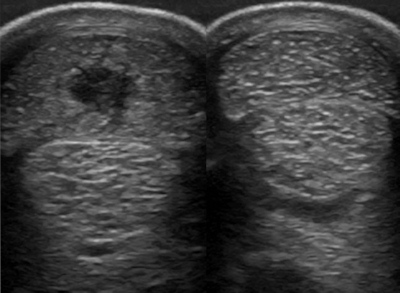

图左为受伤肌腱的b超显示,图右为正常对比。可见图左位于最上方的指浅屈肌腱体积变大(肿胀),中间出现深色区域(损伤)。

B超检查在治疗筋腱软组织损伤中尤为重要,在整个治疗过程,B超可以探查出病变部位的受损情况和恢复状况,兽医会根据B超探查的结果,制定下一步的治疗和恢复计划。